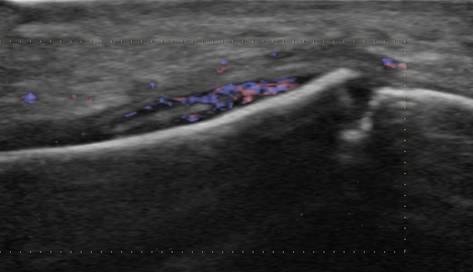

Tụ mủ dưới màng xương

Viêm xương tủy

» Thông tin: Nam giới – 11 tuổi.

» Lâm sàng: Sưng đau cẳng chân.

# Tụ mủ dưới màng xương.